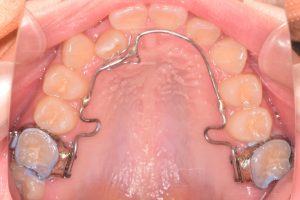

リンガルアーチ

2ヶ月

0000000013

0000000021

上顎の第二大臼歯も萌出し

上下左右の第一大臼歯の関係も改善したため

2期治療(インビザライン)

に移行しました。